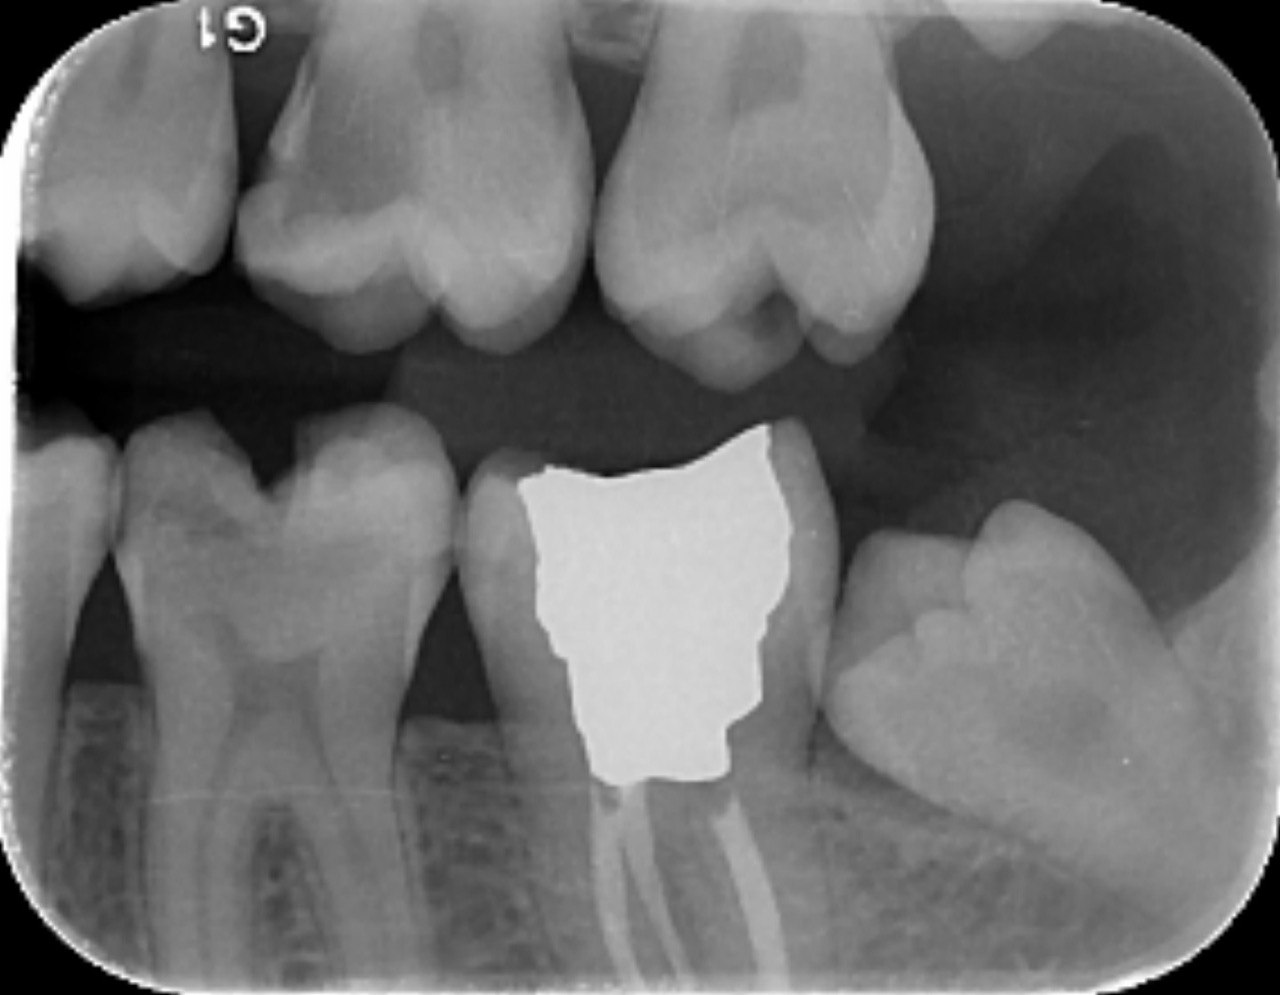

14. Which surfaces shows recurrent caries?

15. Which surface shows recurrent caries?